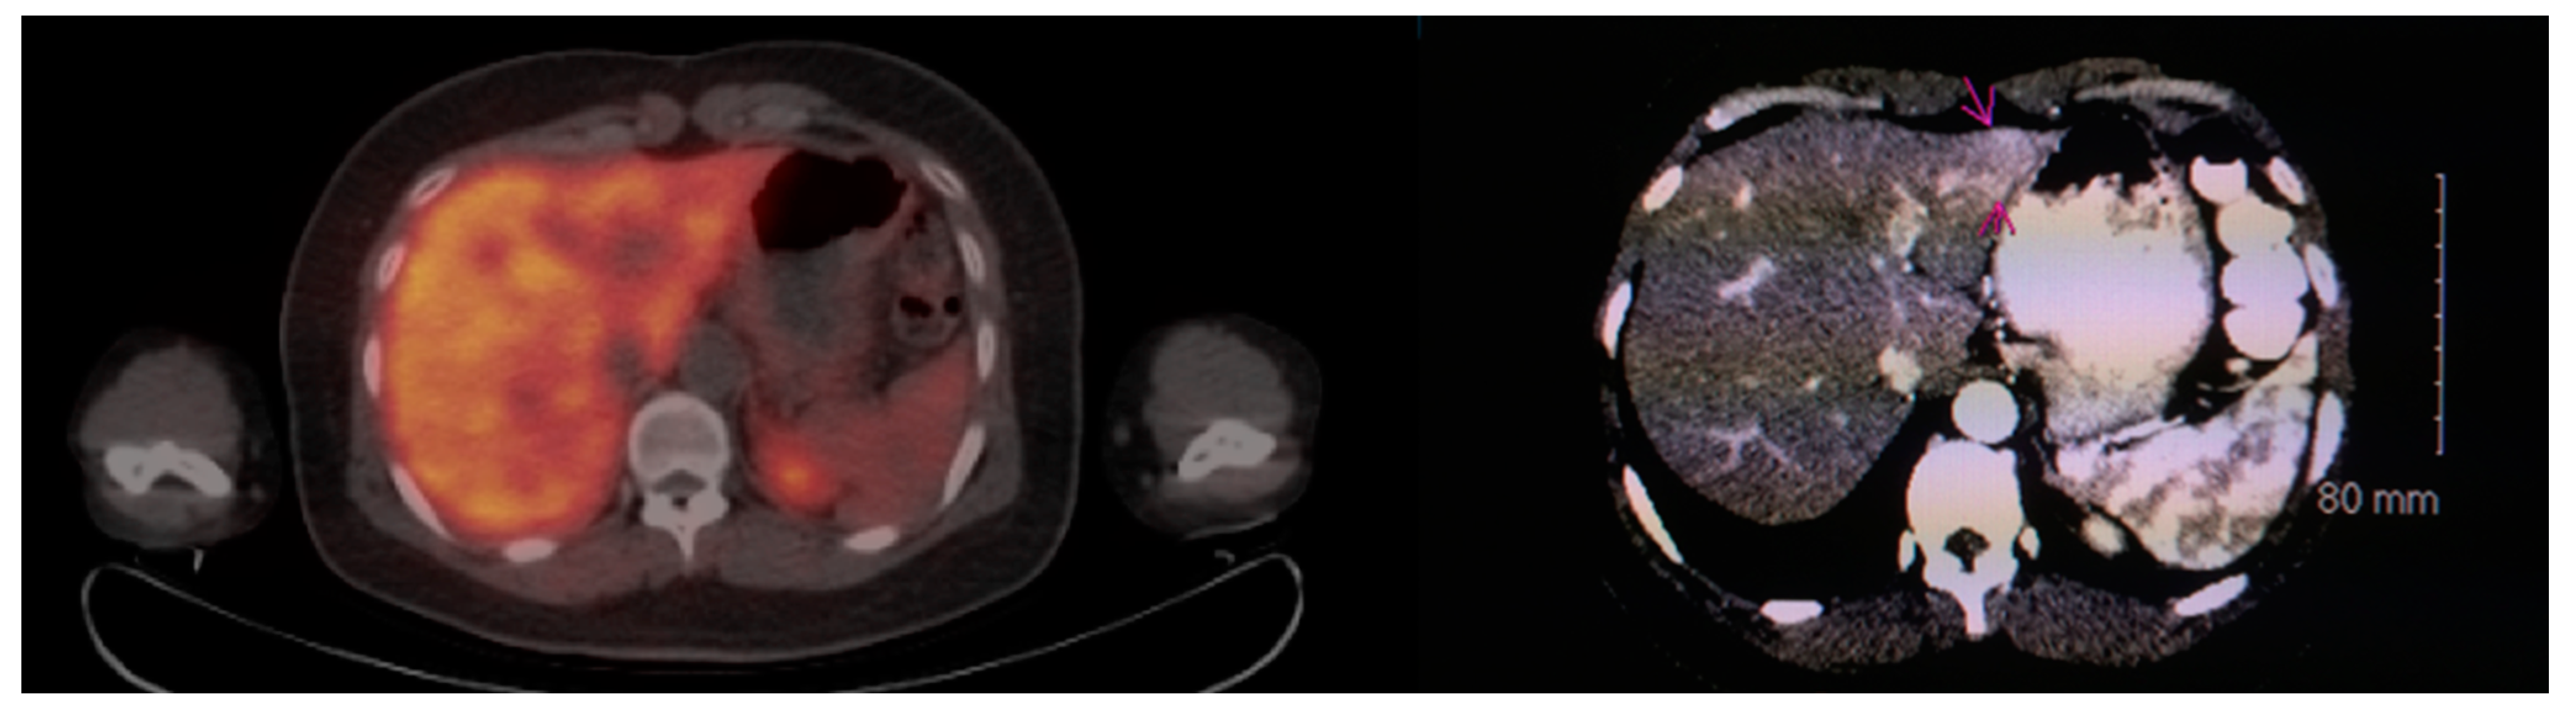

Multiple foci of increased FCh uptake in the liver consistent with multifocal or multinodular HCC (example, Figure 1) were noted in 8 of the 13 patients with increased primary tumor uptake. Of these, the areas of increased FCh uptake were adjacent to the treatment site (examples, Figure 2 and Figure 3) in 2 patients treated by local tumor ablation and 1 patient treated by liver resection. In one newly diagnosed case, PET demonstrated heterogeneous tumor FCh uptake with increased peripheral uptake and markedly diminished central uptake (Figure 4). Pathology in this case revealed a highly-necrotic tumor with Edmondson-Steiner grade 3 differentiation.

Figure 2.

Recurrent HCC surrounding previous radiofrequency ablation site. PET/CT (left) shows absent FCh uptake (white arrow) in an area of the liver where HCC was previously treated by radiofrequency ablation. Corresponding PET (right) clearly shows multiple foci of increased FCh uptake surrounding the ablation site consistent with recurrent HCC (arrows). A pulmonary metastasis was also detected in this patient (arrowheads).